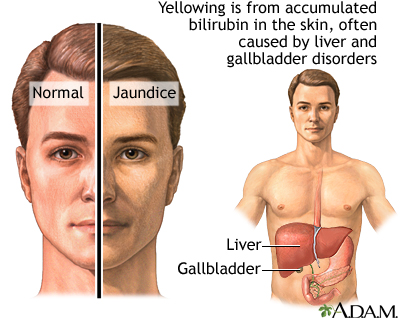

form in the stomach, the lower part of the esophagus, and at times the rectum. They transport the blood diverted from the liver. - Bilirubin, a substance found in bile, also builds up in the bloodstream, resulting in

jaundice

, a yellowish discoloration of the skin and eyes, as well as dark-colored urine. - Fluid buildup in the abdomen (called

jaundice

) due to buildup of bilirubin. - Itching (

Jaundice is a condition produced when excess amounts of bilirubin circulating in the bloodstream dissolve in the layer of fat underneath the skin, causing a yellowish appearance of the skin and the whites of the eyes.